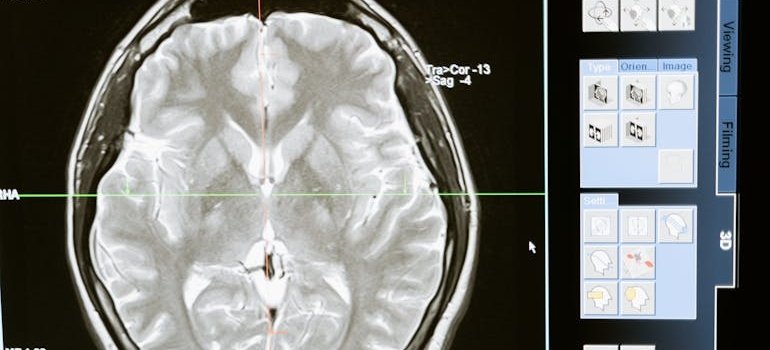

MRI of a brain.

Psilocybin affects the brain by binding to serotonin receptors, altering perception and mood.